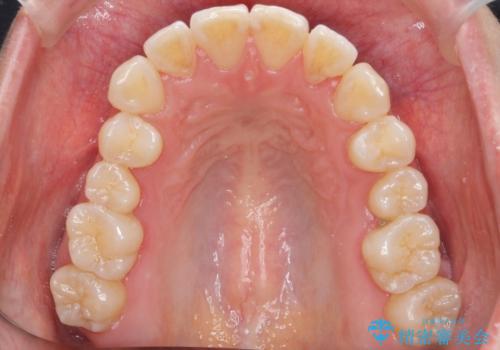

下の前歯を中に入れるためにIPR(歯をわずかに削る処置)を行いました。

左上の反対咬合になっていた歯の頬側咬頭は、すでに削れて短くなっていましたがそのまま並べています。